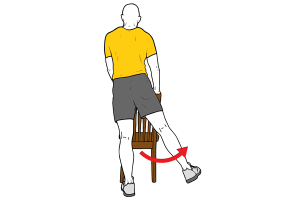

Existen dos tipos de pie plano, el flexible y el rígido. El pie plano valgo flexible es aquel que se produce por una alteración de la musculatura intrínseca y extrínseca del pie, así como por una laxitud muy pronunciada de los ligamentos que dan estabilidad a las numerosas articulaciones del pie. Para diferenciar si un pie plano es flexible debemos colocar a nuestro pequeño de pie en el suelo sobre una superficie estable y dura. Si al ponerle de pie, vemos como su arco plantar interno se derrumba y por lo tanto el pie se aplana por completo haciendo que el talón se desvía hacia interno, nos encontramos ante una falta de tono muscular y una posible patología. Para comprobar si es flexible, le vamos a pedir al niño que sin sujetarse en ningún lado o con una pequeña ayuda por nuestra parte, se ponga de puntillas con ambos pies. Si al realizar este gesto y al ponerse en una posición máxima, apoyando todo el peso sobre la base de los metatarsianos y los dedos el arco del pie aumenta, hablamos de que nos encontramos ante un pie plano valgo flexible. Por norma general el pie plano flexible en los niños no suele asociarse con cuadros de dolor, ni una alteración del equilibrio y de la marcha grave. Si que es verdad que podemos tener dificultad a la hora de correr o de realizar desplazamientos por superficies irregulares.

Cuando hablamos de un pie plano rígido nos encontramos ante la misma problemática que en el anterior caso. Cuando ponemos al niño de pie, el arco interno del pie se derrumba. A diferencia del flexible, cuando mandamos al peque ponerse de puntillas, el arco interno no aparece, el movimiento es doloroso y en muchas ocasiones no hay manera de realizar el gesto.

La musculatura sobre la que vamos a trabajar va a ser la siguiente: musculatura intrínseca del pie, tibial posterior, tibial anterior, sóleo y gemelos.

Los ejercicios que desde la fisioterapia vamos a pautar, serán los enfocados a corregir la debilidad de esta musculatura. Siempre teniendo en cuenta, que al tratarse de niños, es mejor integrarlos en juegos y convertirlos en un momento entretenido, aunque deben hacerse de manera consciente y no solo como un simple juego para pasar el rato. La dosis tanto intra sesión como semanal de los ejercicios la va a determinar el estado del pie, la capacidad de atención y la disponibilidad de la familia para realizarlos. Aunque es bueno realizarlos con una alta frecuencia para que el trabajo sea alto.